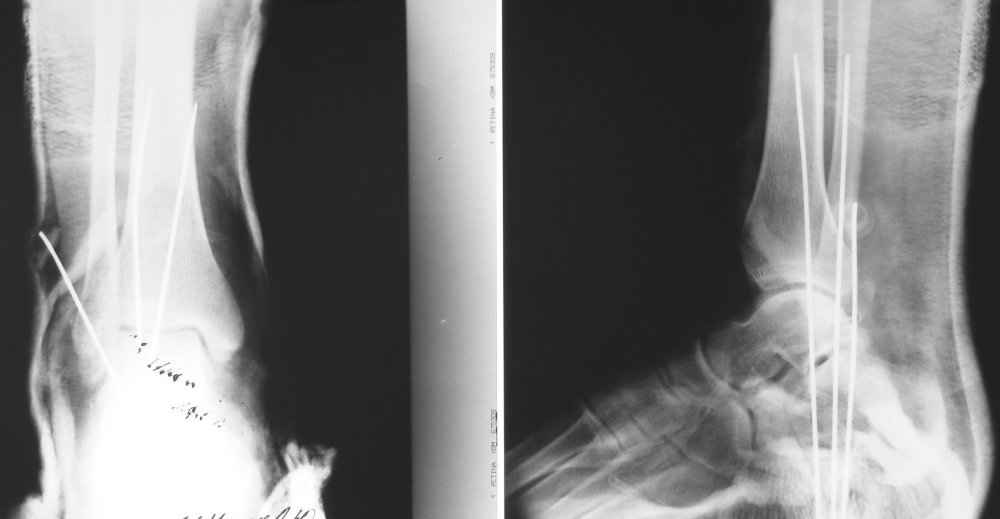

На лечении находится пациент 35 лет. Травма в сентябре 2008 г.- открытый вывих таранной кости

В день травмы ПХО, вправление вывиха, трансартикулярная фиксация. Рана зажила первично. С января нагрузка на конечность. С конца апреля- болевой синдром. На рентгенограммах и КТ признаки ас. некроза таранной кости, артроз подтаранного и голеностопного суставов.